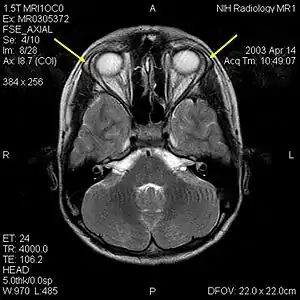

![]() | |

| MRI of the brain of 12-year-old boy with triple-A syndrome showing hypoplastic lacrimal glands (yellow arrows) | |